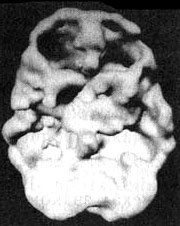

Мозг человека, употребляющего много кофеина и никотина

Трехмерное изображение поверхности, вид снизу. Обратите внимание на выраженное общее снижение активности, особенно в префронтальной коре и височных долях.

Я предложил ему провести сканирование SPECT, чтобы с его помощью точнее определить состояние мозга. Кроме того, наглядные изображения могут стать лучшим аргументом против курения и кофе. Результаты сканирования стали неприятной неожиданностью даже для меня. Активность была заметно снижена по всей поверхности коры, и особенно в области префронтальной коры и височных долей. Я сказал своему знакомому, что ему надо найти другой стимулятор работы мозга, помимо кофе и никотина. В противном случае может получиться так, что он попросту окажется не в состоянии в полной мере вкусить радость успеха — у него не останется на это мозга. На протяжении нескольких недель он держался, но затем вновь вернулся к своим привычкам. И вот мне интересно: или сниженная активность височных долей «помогла» ему забыть то, что он увидел на изображениях SPECT, или очень низкая активность префронтальной коры не дает ему возможности в должной мере управлять собственными импульсами. И хотя я рекомендовал ему попробовать препарат, стимулирующий активность мозга (Ritalin или Adderall), он настоял на том, что хотел бы вылечить свой СДВ «естественным путем».